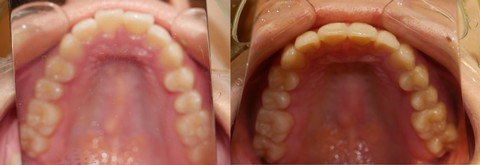

【 出歯、非抜歯、6ヶ月 】

【 出っ歯 をブラケット装着期間 6ヶ月で 】

【 治療期間:2020年7月7日~2021年4月25日、 9ヶ月18日、その中でブラケット装着期間は 6ヶ月13日 】

非抜歯症例